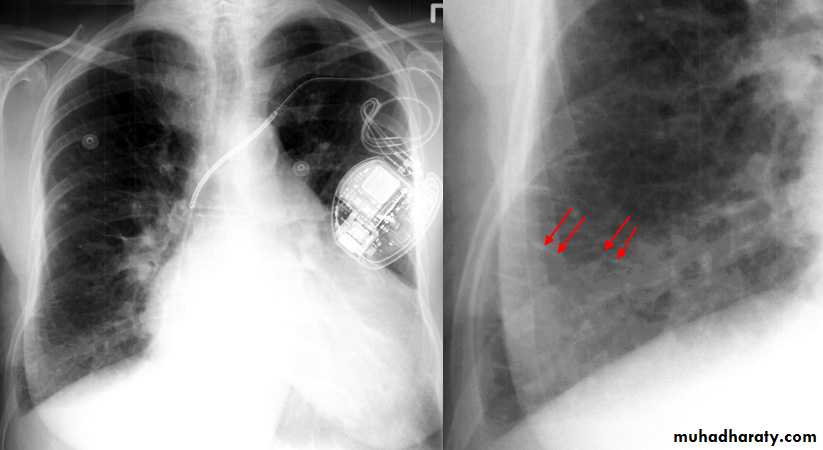

• Alveoiar oedema (‘Bat’s wings’)

• Kerlev B lines (interstitial oedema)

• Prominent upper lobe vessels

• Cardiomegaiy

• Pleura

• effusion

Kerley A lines (Arrows), Kerley B lines (arrowheads)